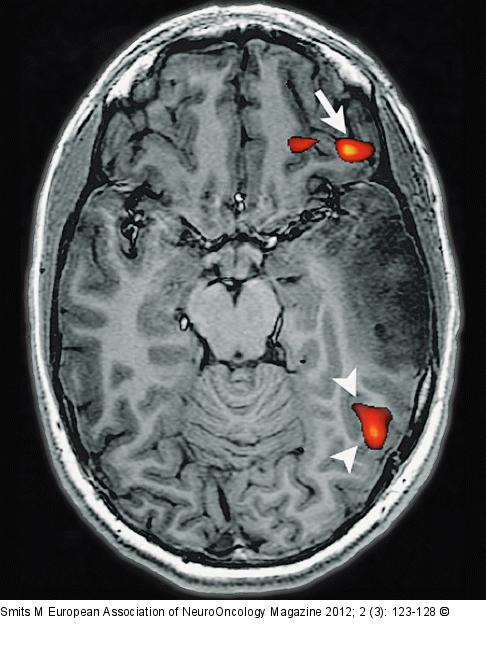

Figure/Graphic 2: Brain tumour Brain tumour localised in the left temporal lobe of a left-handed patient. fMRI activation of a verb-to-noun generation is present in the expressive language area in the inferior frontal gyrus (arrow), as well as in the receptive language areas in the posterior temporo-parietal cortex (arrowheads). Activation is more pronounced in the left hemisphere, indicating a left-lateralised hemispheric language representation. |

Brain tumour localised in the left temporal lobe of a left-handed patient. fMRI activation of a verb-to-noun generation is present in the expressive language area in the inferior frontal gyrus (arrow), as well as in the receptive language areas in the posterior temporo-parietal cortex (arrowheads). Activation is more pronounced in the left hemisphere, indicating a left-lateralised hemispheric language representation. |